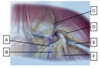

Descrever as estruturas apresentadas:

1) Vasos epigástricos inferiores

2) Ligamento inguinal

3) Vasos espermáticos

4) Nervo femoral

5) Artéria ilíaca externa

6) Veia ilíaca externa

7) Ducto deferente